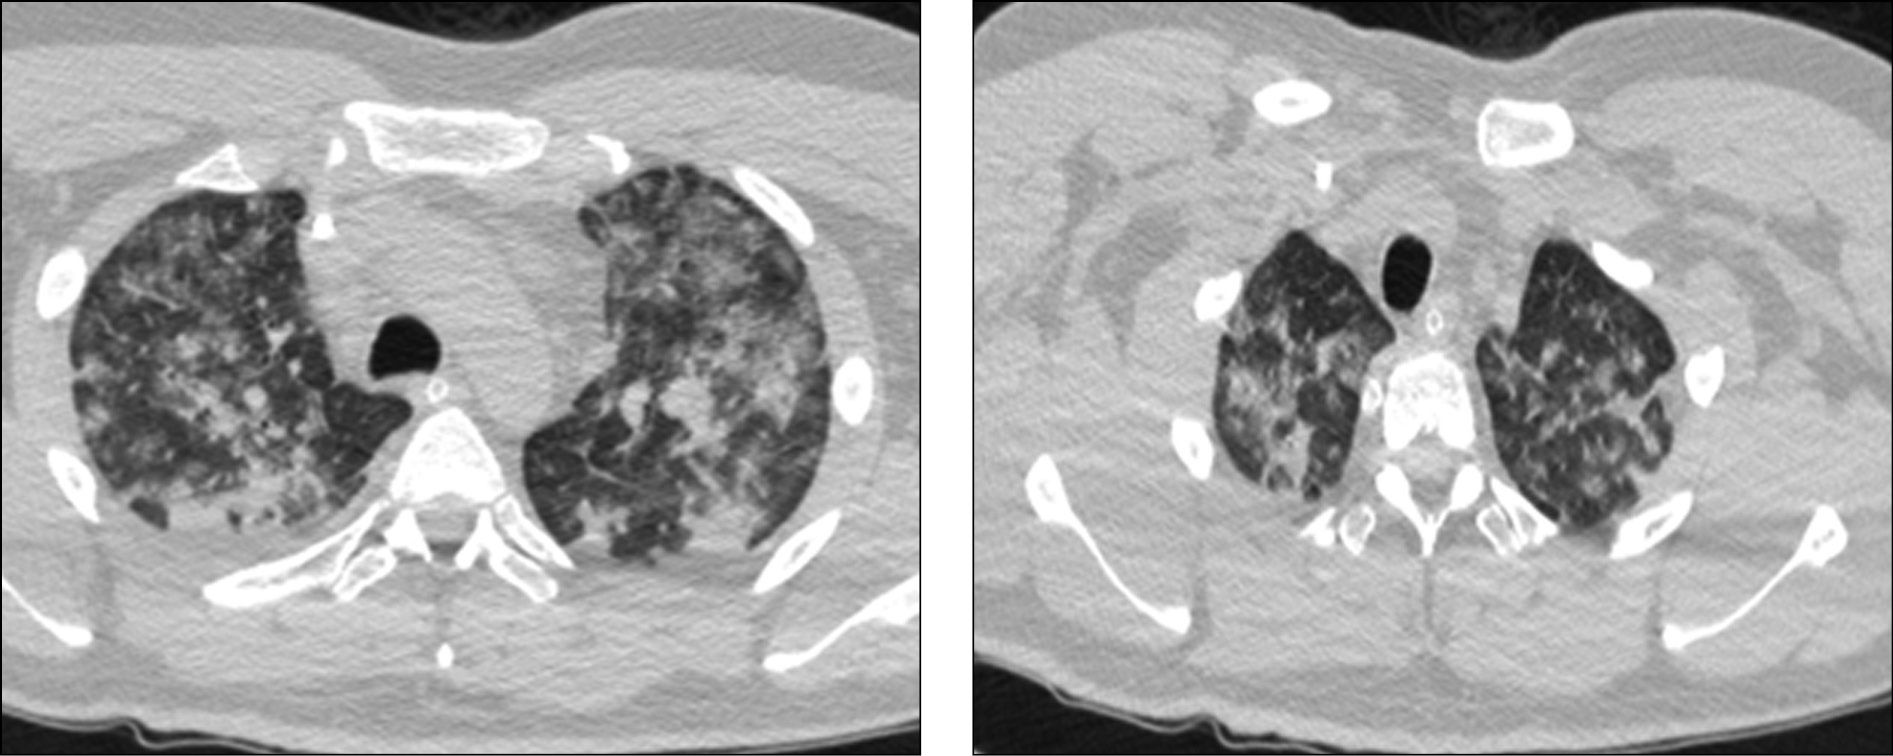

Поражение легких является одним из основных симптомов коронавируса (COVID-19). В данной статье представлены фото рентгеновских снимков, которые позволяют визуально оценить состояние легких при этом заболевании.

Фото рентгеновских снимков поражения легких при COVID-19

На фотографиях рентгеновских снимков видно, как вирус воздействует на легочную ткань. Характерные признаки поражения легких включают пятна, инфильтраты и наличие жидкости внутри легочных альвеол.

Фото рентгеновских снимков помогают врачам и специалистам визуально определить степень поражения легких и принять соответствующие меры лечения и поддержки пациента.